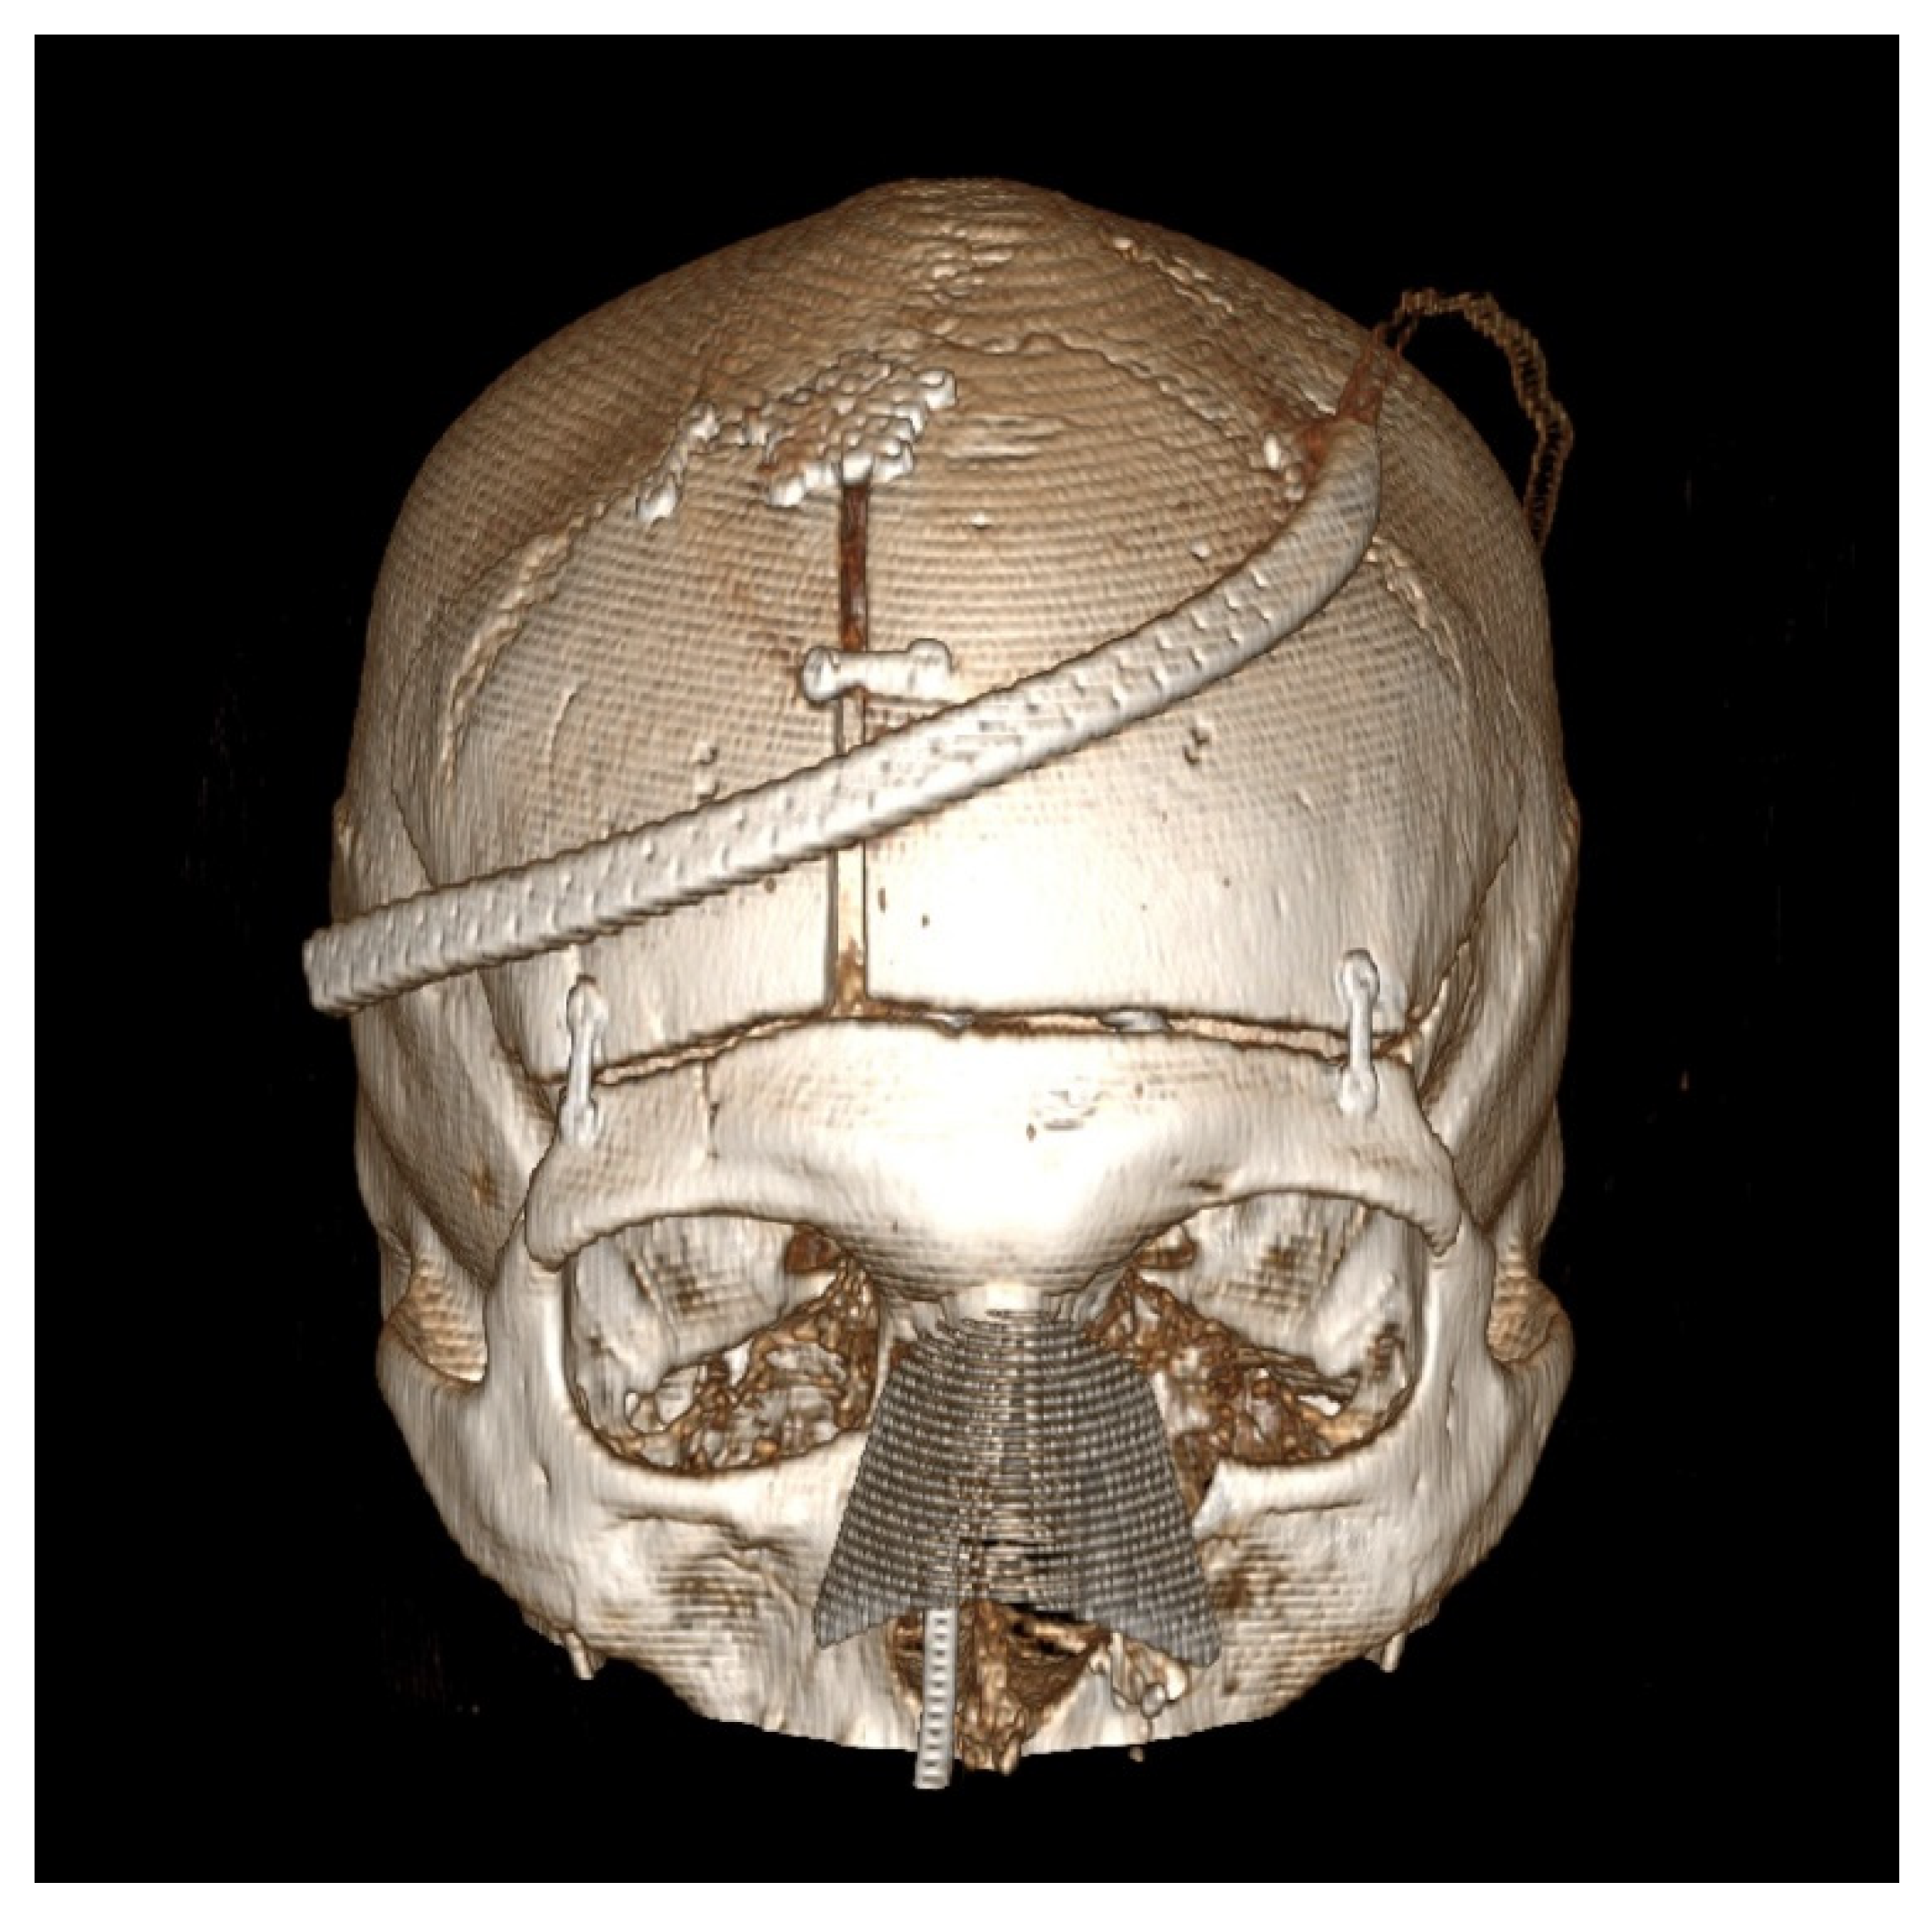

Figure 1D). Avoidance of damaging the temporalis muscle with the drill is important, as is avoiding excessive subperiosteal dissection while performing the above-mentioned steps, as this would render the osteoplastic flap ineffective. For reconstruction, we prefer one small dog bone just medial to each keyhole burr hole, one small dog bone to connect the bone flaps and a burr hole cover at the most posterior paramedian burr hole (

Figure 2). Additional hardware may be used as needed for a flush and even fit of the bone flap to prevent cosmetic deformity.